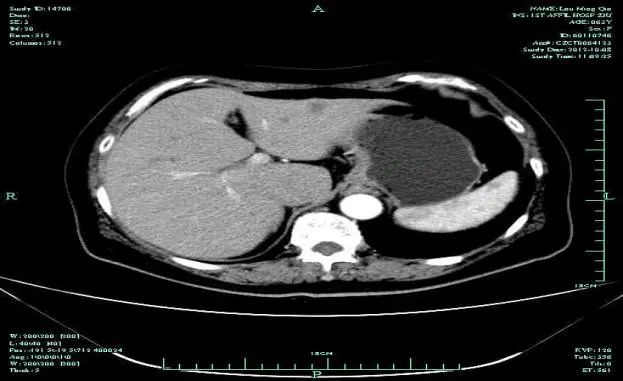

影像学表现:

• CT示:肝转移

CT-T

CT-H1

MR-H1

影像学检查结果评估:cPD。